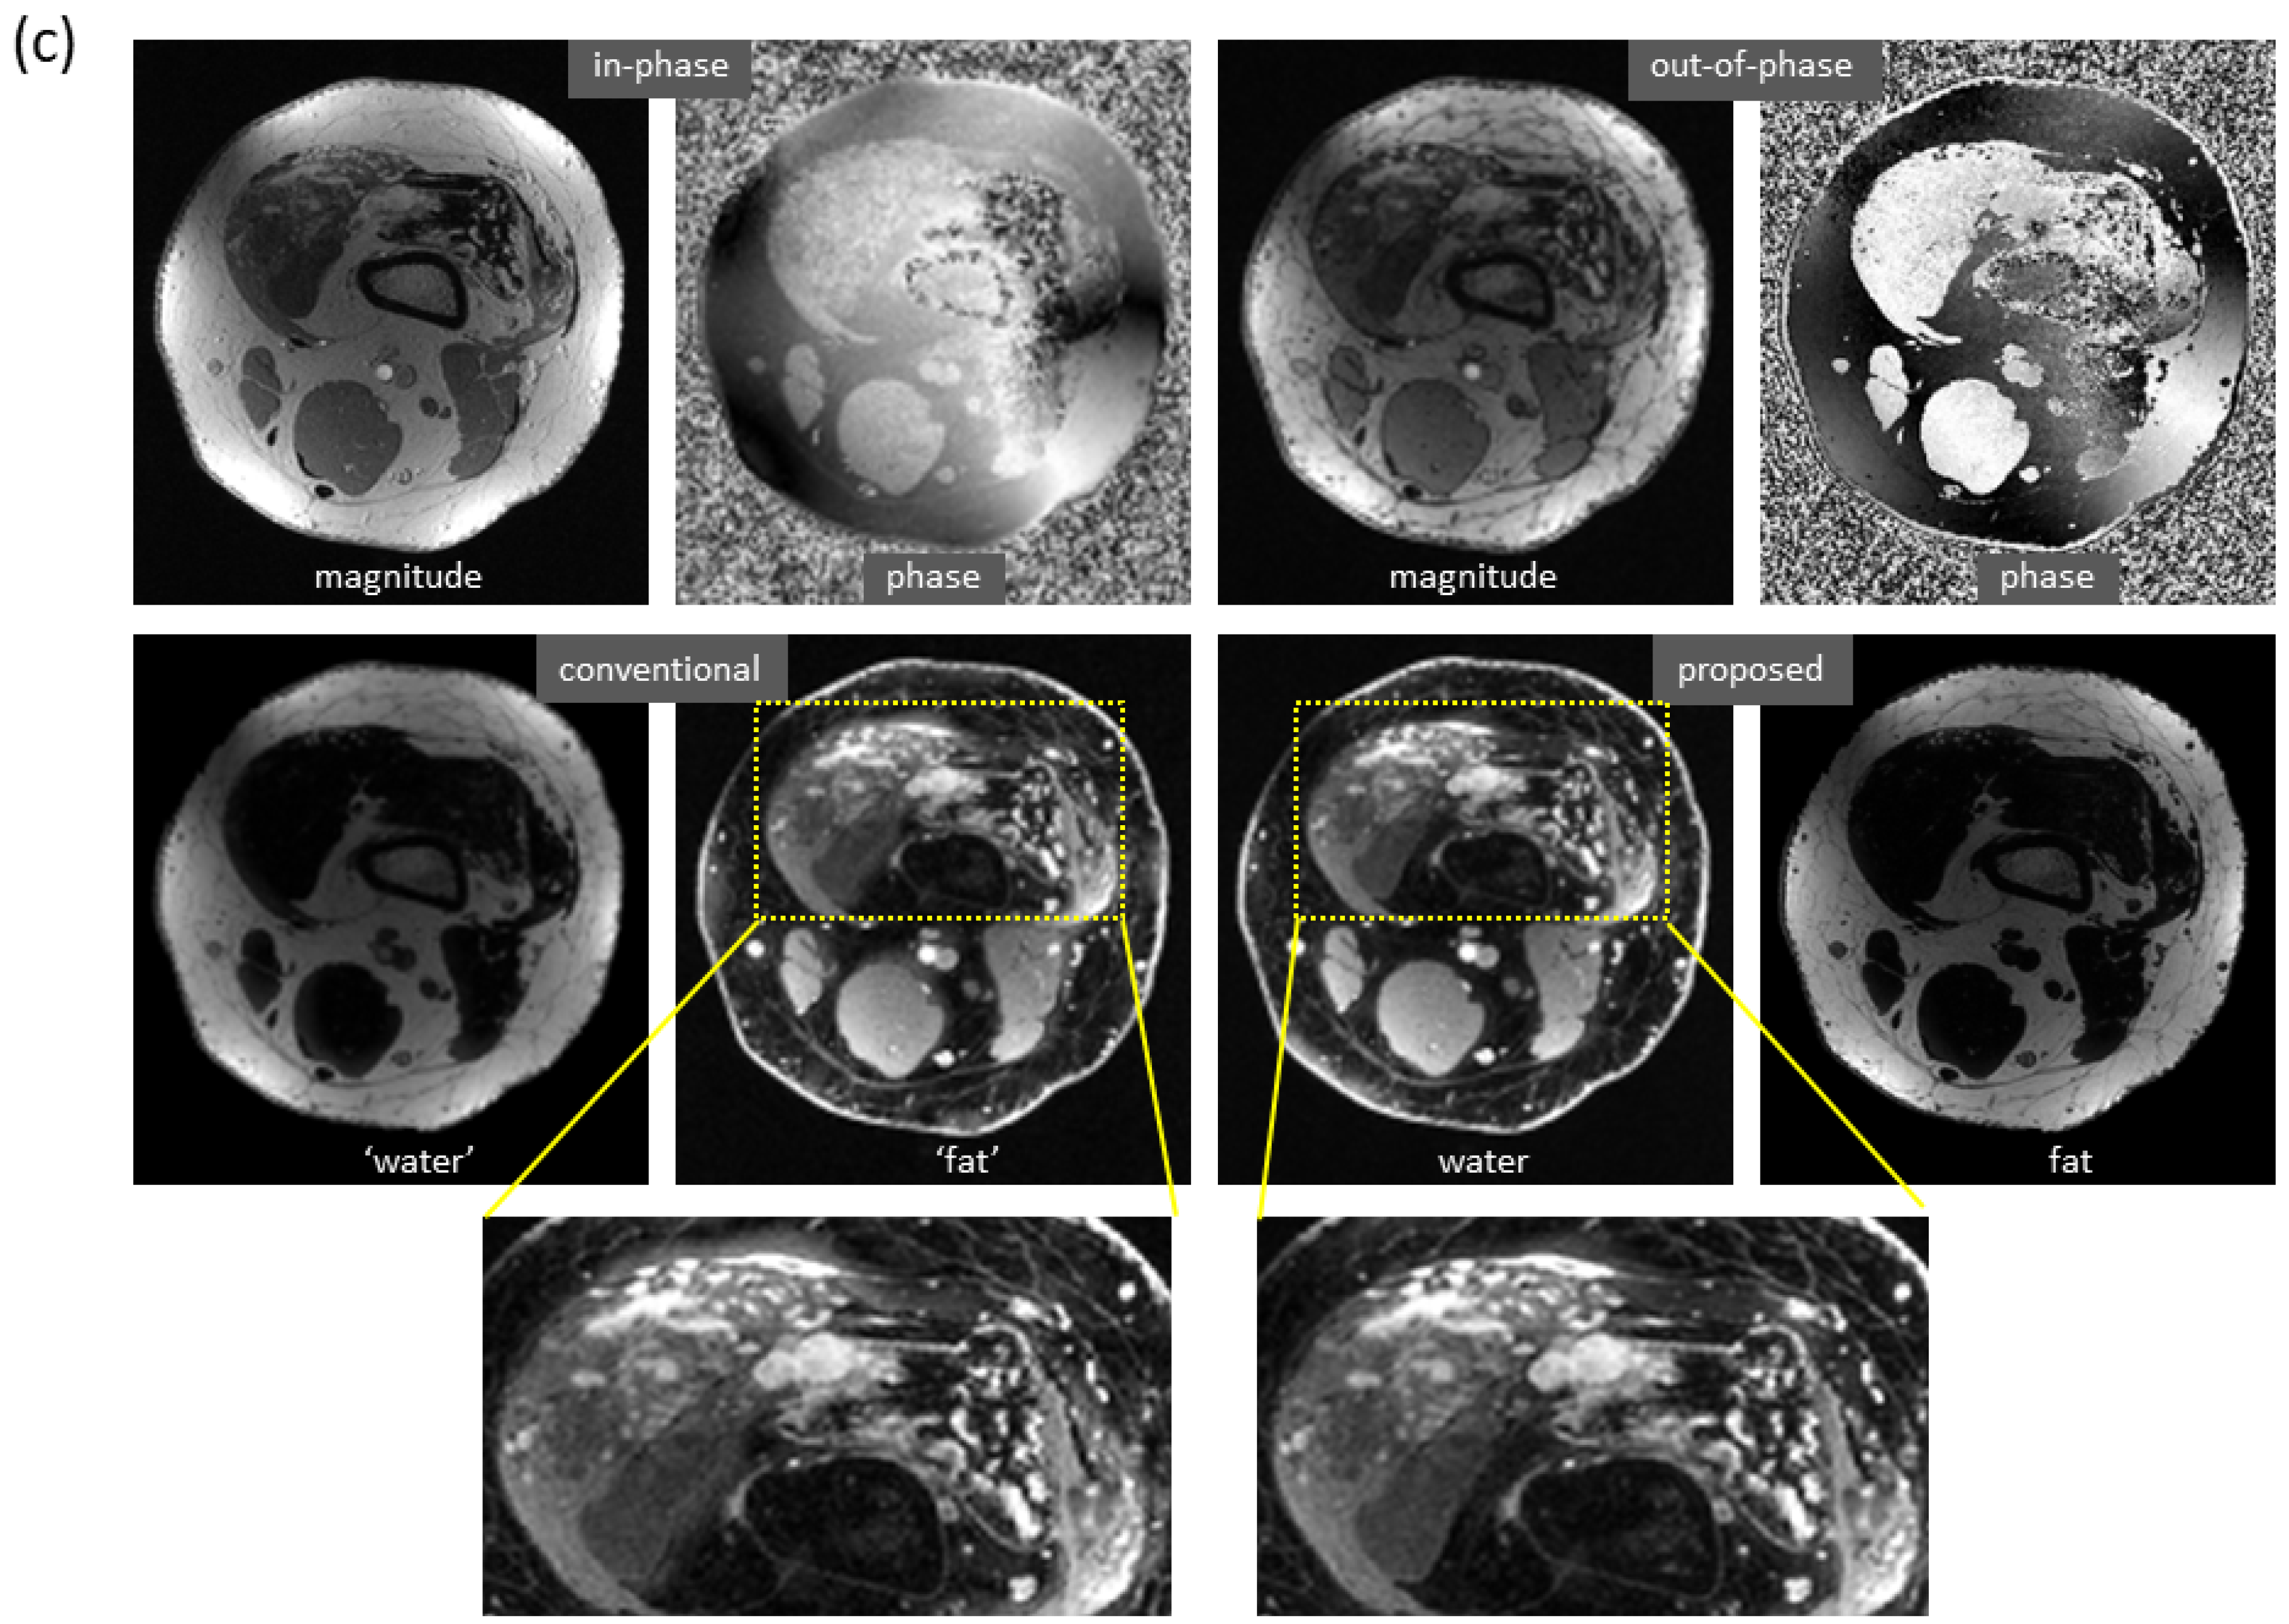

Figure 6 shows the mitigation of severe artifacts induced by a metallic object, further demonstrating robustness to out-of-distribution data. The dramatic changes in local magnetic fields made the cases with metallic implants very challenging. In a knee study (Figure 6a), phase corruption in dual-echo images caused severe artifacts in the reference water/fat images. Interestingly, the predicted images lacked these artifacts. Here, the test images were acquired on a PET-MRI scanner (whereas the majority of training data were obtained on MRI scanners). In an ankle case (Figure 6b), both signal loss and phase corruption were observed in dual-echo images, leading to artifacts in the reference images. The metal artifacts, along with additional water/fat swaps that occurred in peripheral region of off-isocenter slices, were corrected in the predicted images even though the ankle images were acquired on a 1.5T MRI scanner (while training data were obtained on 3T scanners). Of note, for these two cases, is the fact that the training sets lacked any examples with metallic implants.

Figure 6.

Marked reduction of metal-induced artifacts, where the training set lacked any examples with metallic implants. (a) In this knee case acquired on a PET-MRI scanner, severe off-resonance artifacts occurred in the reference images since the local magnetic field near metal changed dramatically (as can be seen from the input phase images). In the predicted images, metal-induced artifacts were largely corrected. (b) In another ankle case acquired on a 1.5T MRI scanner, signal loss (blue arrow) and phase corruption (red arrow) were observed in the input images, resulting in artifacts in the reference images (yellow arrow). In addition, severe water/fat swaps (green arrow) occurred in the peripheral region of this off-isocenter slice. Both metal artifacts and water/fat swaps were mitigated in the predicted images, even when the model was trained with only knee images acquired on 3T scanners.